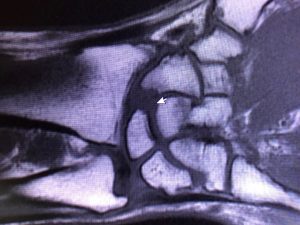

Här opereras MRF:s Joachim Due-Boje i höger handled för en arbetsskada. 30 års mekande med långvarig användning av vinkelsnurror och bankande på lednycklar och dylikt mot bultar tog ut sin rätt på en led. Nu har ortopeden slipat ner skelettytorna där brosk saknades för att lindra värken.